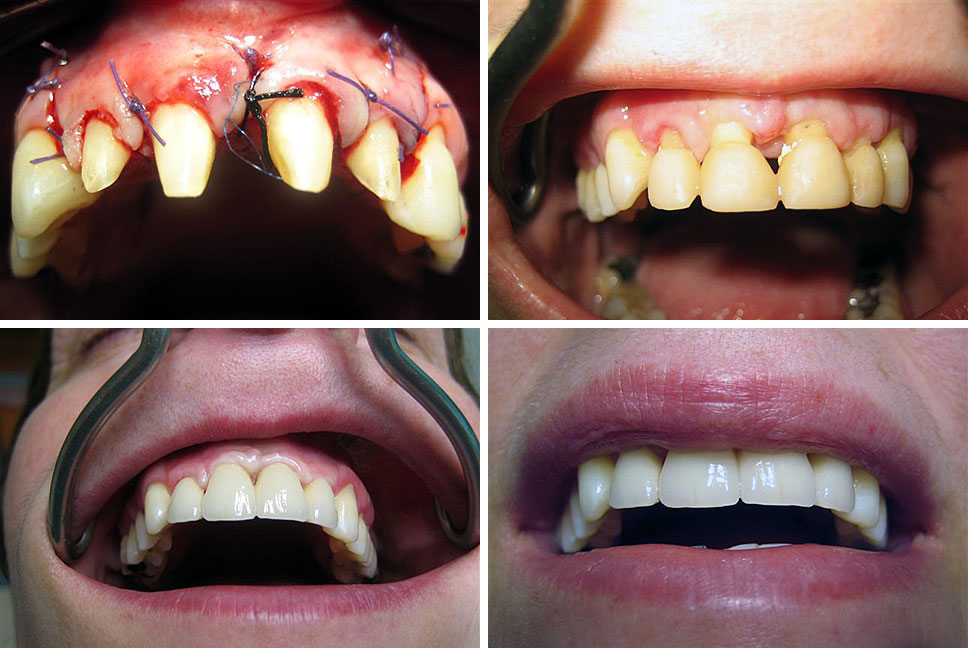

Estetska dentalna medicina